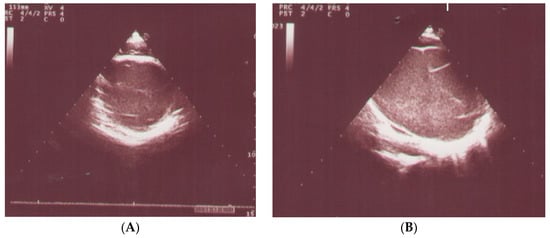

The electrocardiography (ECG) detected sinus tachycardia with normal axis (Figure 1). Although plane chest radiography was normal, an apical four-chamber view echocardiography showed an echolucent space next to the posterior wall of the left ventricle with compression effect (Figure 2). The mass was extrinsic and confined to the pericardium. The right and left ventricular chamber size and function were normal, and there was no valvular heart disease. Then, a chest CT scan with contrast showed a retrosternal mass characterized with a clear serous fluid with compression on the posterior wall of the left ventricle (Figure 3). To rule out the causes, inflammatory factors, blood culture, viral antibodies, collagen vascular markers, sputum acid-fast bacilli (AFB) and PPD test results all were normal.

Figure 2.

Echocardiography showed an abnormal mass in the posterior wall of the left ventricle. (A) Parasternal Short Axis view. (B) Left ventricle pericardial cyst. (C) Parasternal Long Axis view. (D) Apical 4-chamber view.